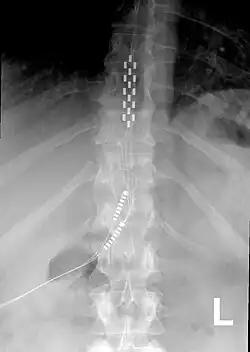

Neurostimulation for chronic pain is primarily through the use of spinal cord stimulators.[11] These devices deliver electrical stimulation to different areas of the spine based on where they are implanted. Since 2012, Medtronic has produced spinal cord stimulators with accelerometers that can predict the patient's position. The device can be programmed to give additional electrical stimulation if the patient is thought to be in a more painful position.[12]